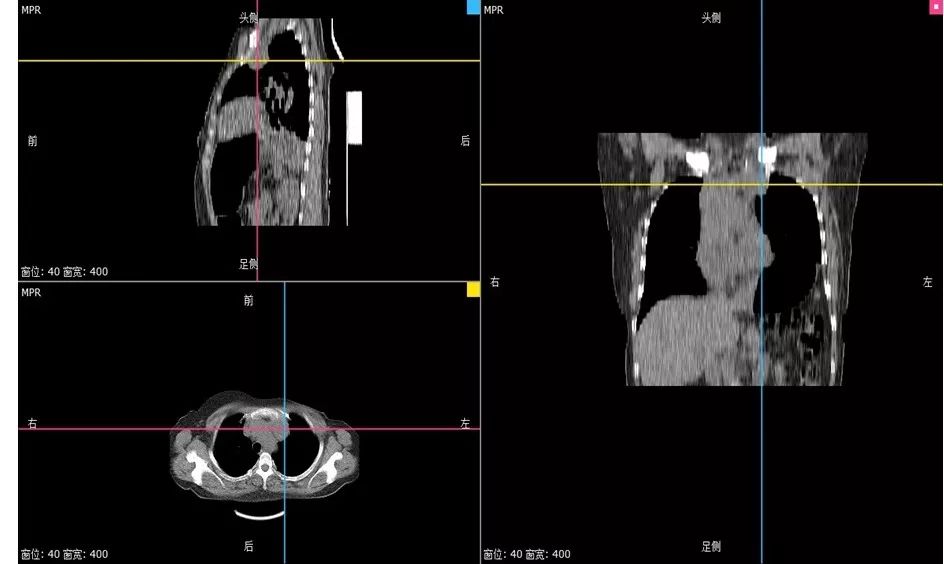

接受TC(卡铂)+曲妥珠单抗单周方案治疗。治疗2个周期后复查:淋巴结彩超示:左锁骨上淋巴结缩小,大的0.6×0.4cm;复查胸部CT示:左侧纵隔肿物缩小,最大截面约6.0×2.9cm。治疗4个周期后再次复查,淋巴结彩超示:左锁骨上淋巴结缩小,大的0.6×0.4cm;复查胸部CT示:左侧纵隔肿物缩小,最大截面约3.1×2.4cm。治疗6个周期后再次复查,淋巴结彩超示:左锁骨上淋巴结缩小,大的0.3×0.3cm;复查胸部CT示:纵膈肿物缩小明显,病灶局部包绕头臂静脉,与胸壁边界不清。评价治疗有效,继续行TC(卡铂)方案化疗+靶向治疗。治疗8周期后再次胸部CT示:纵隔肿瘤缩小明显,最大截面由最初的7.2×2.9cm缩小为2.7×2.9cm,评价为PR。8周期治疗后,患者出现腹泻,大便次数8-10次/天,水样便,影响日常生活,根据NCI分级属3级重度腹泻。10天左右缓解;II度骨髓抑制。患者拒绝继续化疗,曲妥珠单抗改为21天/周期。

图6. 治疗过程中胸部CT病灶变化